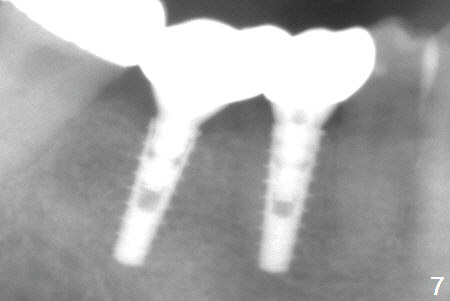

After incision, the ridge at #29 and 30 is found ~ 5 mm wide buccolingually. To place a 4x11 mm IBS implant at #30, the ridge is expanded using BEB technique (bone expansion and bending, Fig.1). It appears that the initial osteotomy at #29 is mesial (Fig.1 yellow dashed line: the distal surface of the root of the tooth #28). After moving the osteotomy distal, the final implant position at #29 (4x11 mm) is within normal limit (Fig.2). The bone at #29 seems to be not so dense that bending (using 1.6 mm drill) is not necessary (using Magic Split and Magic Expanders 3 and 3.8 mm). Later the implant at #30 (4x11 mm) is placed deeper (Fig.3). After placing bone graft around the implants/abutments and suturing, the ridge looks wider with apparent formation of the gingival bands around the abutments (Fig.4 *). Three months and a half postop, bone loss is minimal (Fig.5) and gingival bands forms around the abutments (Fig.6). Fig.7 is taken 1 month post cementation (panoramic X-ray). The patient chews normally 1 year (Fig.8) and nearly 2 years (Fig.9,10) post cementation. The crown at #31 needs recementation 2 years 7 months post #30 cementation; the incomplete seating of the abutment was noted for the first time (Fig.11). Five months later the patient is going to be retired and wants to travel abroad. After approval, the access hole was reopened; articulating paper shows under occlusion of the crown (Fig.12). Since the gap between the abutment and the implant is large, the abutment/crown complex seems to be necessary to be turned (Fig.13 curved arrow). The proximal surfaces of the crown need to be trimmed (straight lines). After turning, the crown sits down with screw tightening; the patient feels pain from the gingival cuff (Fig.14). After turning, the abutment appears to be completely seated (Fig.15). In fact the mesial and distal surfaces of the crown should have clearance from the neighboring teeth (Fig.14) so that pick-up impression is able to hold the crown/abutment complex securely (Fig.16: *). The crown is separated from the abutment after crown repair. They are seated together (loose connection) using the crown as a guide to seat the abutment. BW is taken without the crown. It appears that the abutment remains seated completely (Fig.17). The apical space is equal between #29 and 30 (Fig.17, as compared to Fig.5).